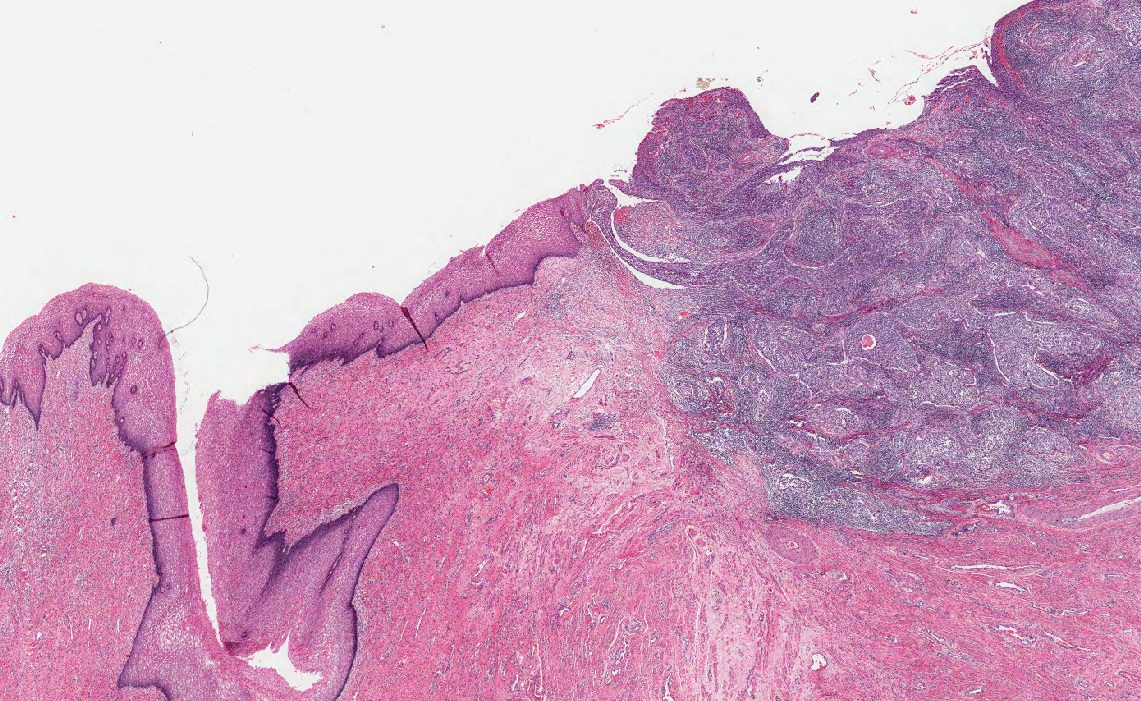

Changes can occur at the macroscopic or gross level, which means you can see the changes with your eyes or they can happen at the microscopic level, which means you need a light microscope or an electron microscope to see the changes. Histopathology is the study of the tissues to identify changes at the cellular or microscopic level.

We saw from the previous example that pathology is also a medical specialty (you need to be a doctor). There are different specialties within Pathology. Anatomic Pathologists look at tissues and organs to determine disease based on changes in the appearance of cells, tissues and organs, both grossly and microscopically and often specialize in a particular organ system. Forensic Pathologists look specifically at why a person has died and so examine the whole body as well as specific tissues and organs and also order toxicological tests to look for foreign substances in the body that may have contributed to the death. Neuropathologists specialize in the nervous system and muscle pathology. Hematopathologists specialize in changes to the blood cells and has Transfusion medicine as a subspecialty. Medical Microbiologists isolate, grow and identify micro-organisms that cause disease, along with which treatments may be effective against them. They work with Infectious Disease specialists to identify and treat communicable diseases and prevent their spread in the community. Medical Biochemists and Clinical Chemists look after the laboratory testing of chemical substances in the body, either produced by the body or ingested; determining what is the best method to use, what the limitations of the tests are, and what are the normal ranges of values for a given test.

Pathologists do not work in isolation. They are supported by a team of Medical Laboratory Technologists, who prepare specimens, run the tests, and trouble shoot problems with techniques and instrumentation. Medical Laboratory Technologists cover a wide range of areas from phlebotomy (drawing blood), to preparing histological samples, to growing up microorganisms, to running complex chemical analysis equipment. Therefore, they tend to specialize as well.